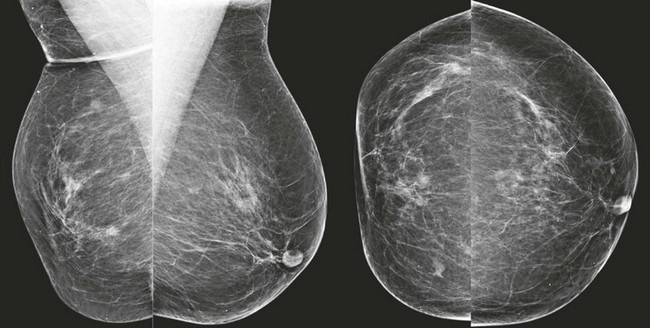

CASE 8-7. Screening mammogram of a 72-year-old woman with a history of lumpectomy and radiation therapy for right breast carcinoma. What are the findings? What do you recommend?

CASE 8-7. There is postsurgical deformity of the anterior right breast. Multiple masses are present in the right breast. Some of the masses (arrows) have indistinct margins. The findings are suspicious for recurrent carcinoma. Diagnostic views and US are recommended.

Magnification views confirm multiple masses, one with spiculated margins (arrow). US reveals three solid masses. Core biopsies of two masses both revealed IDC and DCIS.